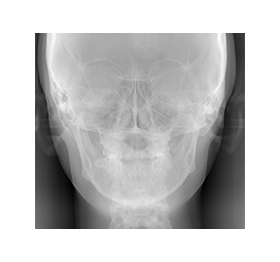

精密検査

矯正治療の前に、精密検査を行います。歯や顔の写真、歯や頭部のレントゲン写真、歯型の採取などを行い、現在の状態を正しく把握します。症状に応じて顔面形態、顎の関節など細かい部分の検査、分析も行います。

レントゲン写真を元に、

歯並びと

顎骨の分析をします

矯正カウンセリングにこられた方へ、WEBCEF(ウェブセフ)よる歯列矯正の解析レポートを作成し、詳しいご説明の上でご提供します。

この解析レポートでは、

・歯並びの左右の傾き

・お顔の中心に対して上顎歯列と下顎歯列がずれていないか

・ずれている場合には、どのように改善できるか

などを分析します。

精密検査料

パノラマレントゲン・セファロ矯正レントゲン・写真撮影の費用分析したデータを基に診断を行い、次回に診断結果をご説明します。